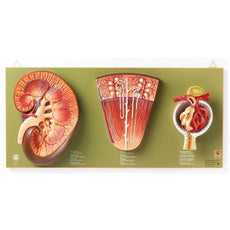

This Urinary System all-in-one-model shows:- Structures of retroperitoneal cavity

- Large and small pelvis with bones and muscles

- Inferior vena cava

- Aorta with its branches including iliacal vessels

- Upper urinary tract

- Rectum

- Kidney with adrenal gland.

One front half of a kidney is removable from the anatomical model of the urinary system. With easy to change male insert (bladder and prostate, front and rear half) and female insert (bladder, womb and ovaries, 2 lateral halves) the Urinary System model is a great teaching tool.

Dual Sex Urinary System model on baseboard.